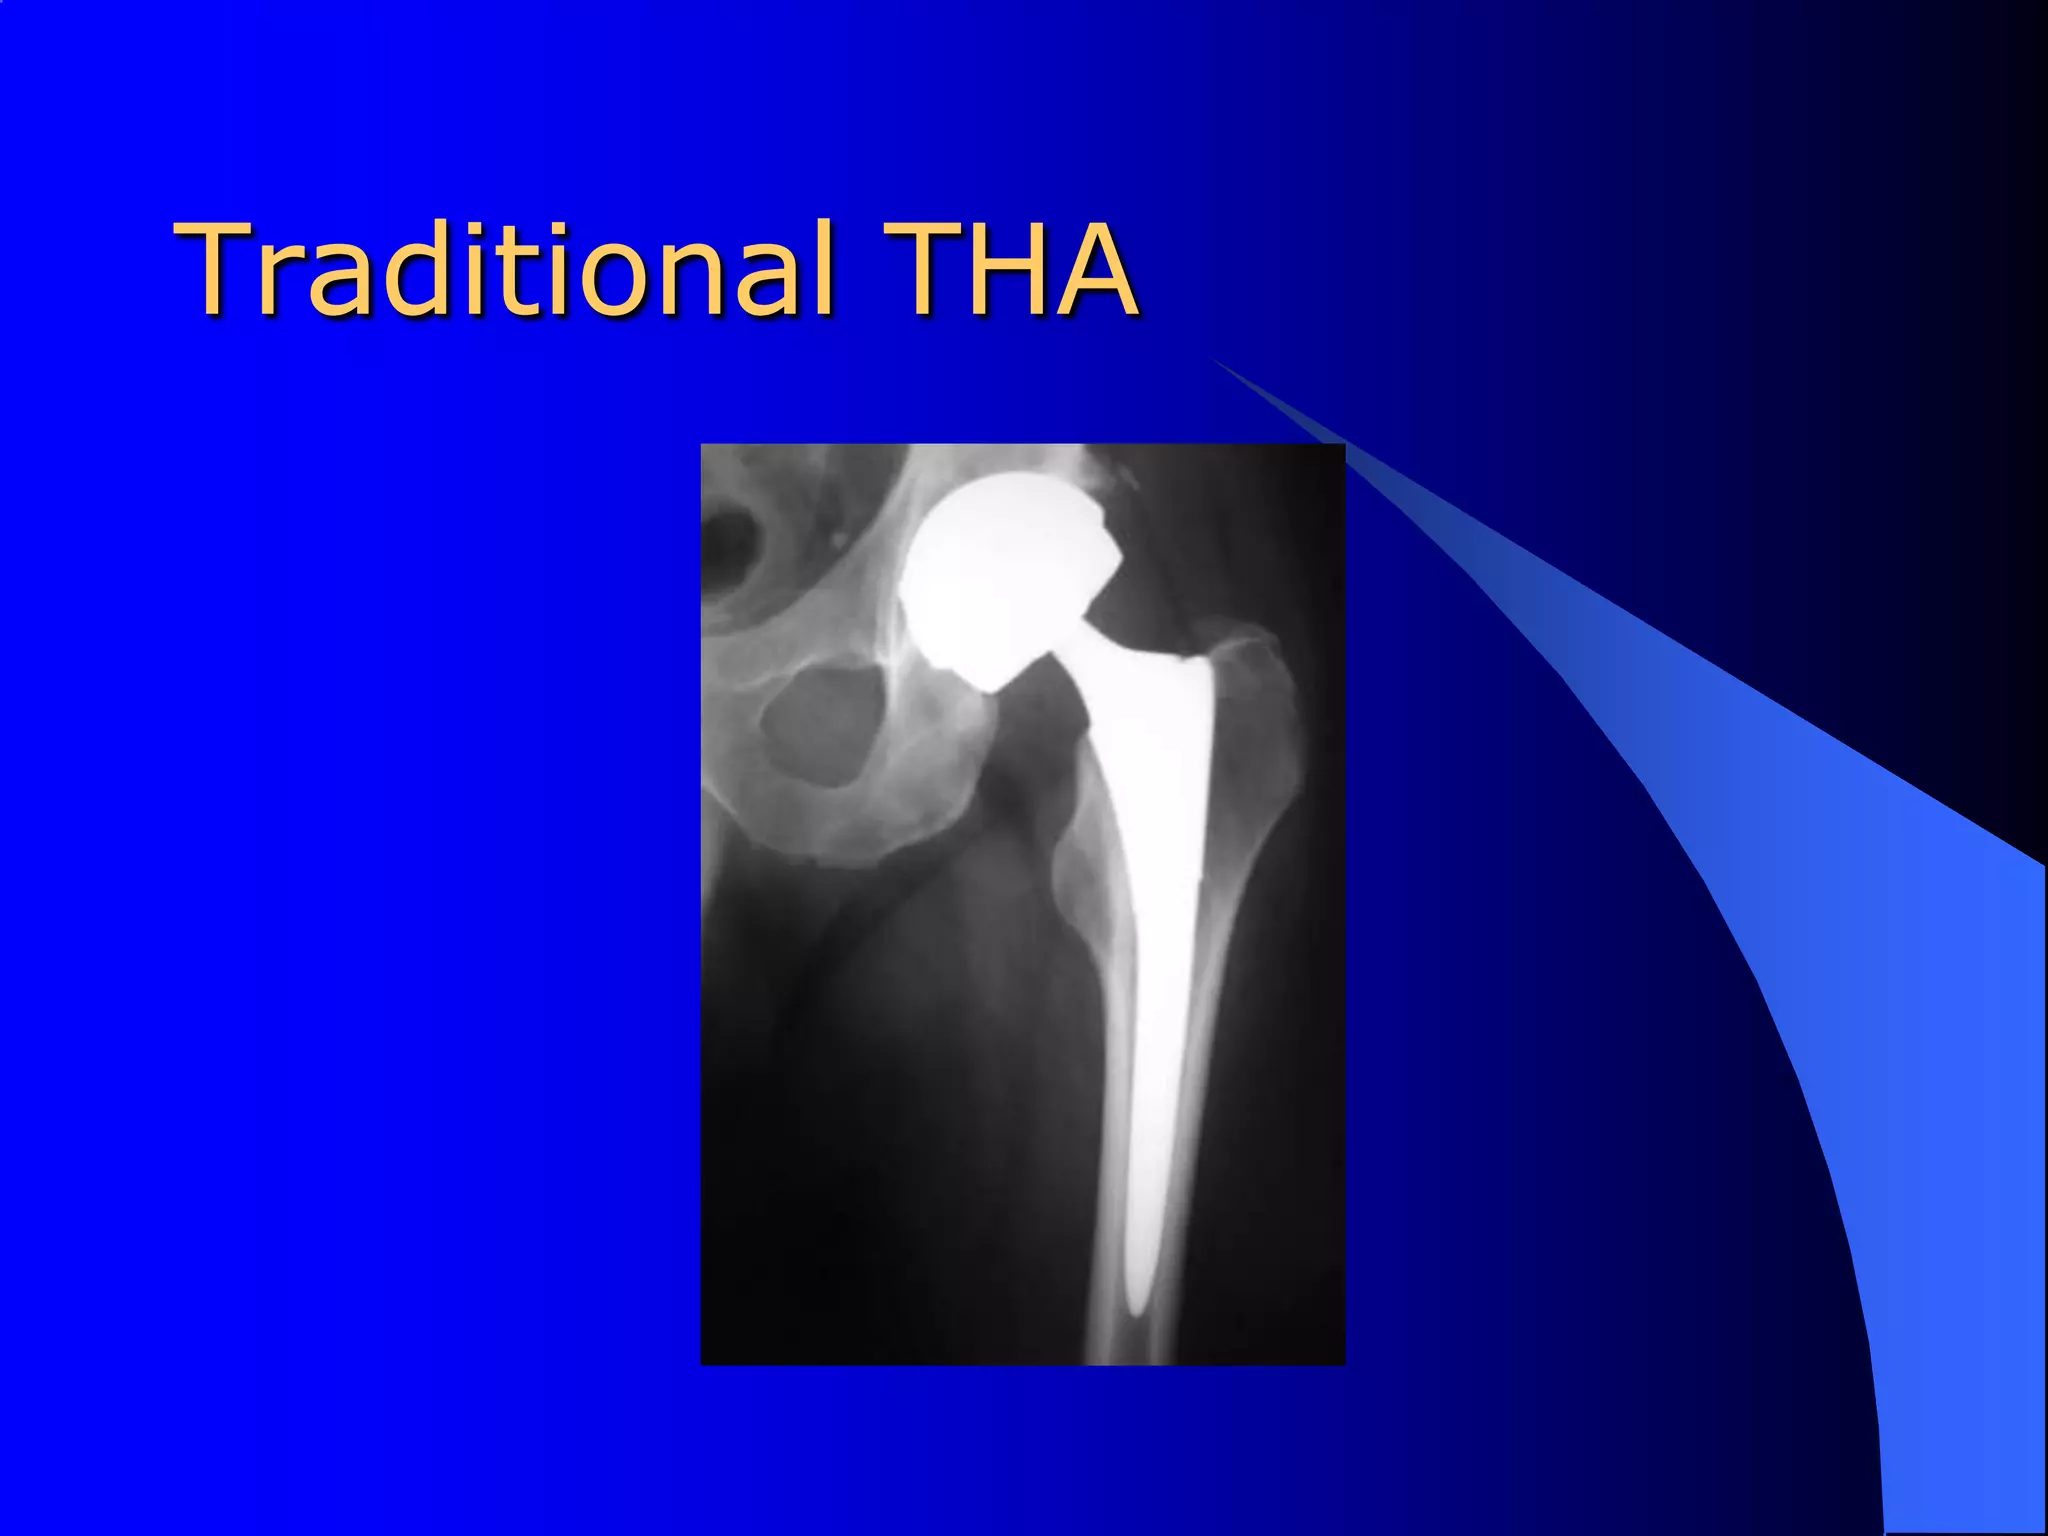

Traditional THA

Total Hip ArthroplastyThe most common surgical procedure for end-stage hip osteoarthritis.Primary reason for surgery is pain which interferes with ambulation.

Total Hip ArthroplastyThe first joint replacement, a total hip arthroplasty, was performed in 1936.Most widely performed orthopedic procedure performed on adults.In 2008, the average hospital and physician charge for a THA totaled $ 45,000.